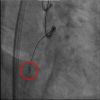

Over the wire, a Stingray balloon (Boston Scientific, USA) was safely advanced and inflated with a side view projection in LAO projection ( Figure 3). Directing the tip of a Stingray wire in RAO projection allowed the tip punctured toward the ventricular side (red circle in Figure 4). Further advancement resulted in a subintimal space ( Video 2).